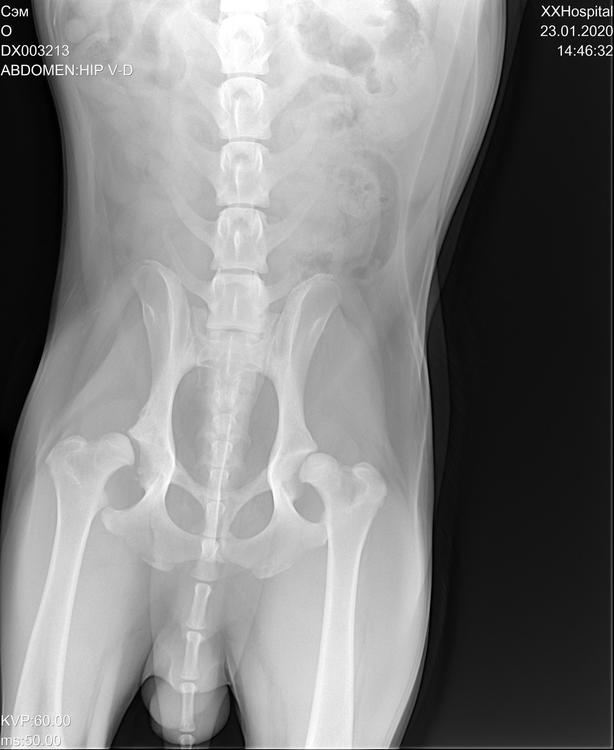

Нужен совет от Пермяков кто делал своим любимцам резекционную артропластику. Нашему лабру 10 месяцев. После активной прогулки захромал на заднюю лапу. Травм ни когда не было. После снимка у Сэма оказалась дисплазия тазобедренных  суставов, на фоне этого произошёл вывих правого тазобедренного сустава, так же имеется подвывих правого сустава!( В клинике травматолог сказал что необходима произвести  резекционную  артропластику. Может кто может посоветовать опытного хирурга этого направления и ортопеда для дальнейшей реабилитации нашего сынишки.662281A7-4F42-4364-BF67-96A6A182DC41.jpeg.f282cb5eff04092dc3c99d25bbb29455.jpeg